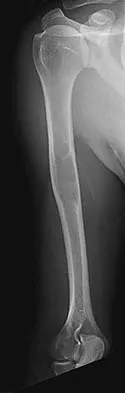

Figures 37a and 37b show radiographs of a 24-year-old man who has a humeral bone lesion that was found during a screening chest radiograph. He denies any symptoms despite leading a very active lifestyle. What is the most likely diagnosis?

Explanation

The radiographs reveal a geographic, diaphyseal lesion with very subtle cortical expansion, cortical thinning, relatively sharp demarcation, and angular rather than rounded borders, suggesting a fibrous bone lesion. This lesion demonstrates the classic ground glass appearance of fibrous dysplasia. Ewing's sarcoma, metastases, and aneurysmal bone cyst all typically have a more aggressive appearance. Parsons TW: Benign bone tumors, in Fitzgerald RH, Kaufer H, Malkani AL (eds): Orthopaedics. St Louis, MO, Mosby, 2002, pp 1027-1035.